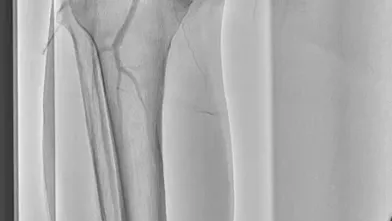

過去にSFAに留置された総長約35 cmの3本のBMSの入口部からの閉塞(動画1)近位端はSFA入口部から1 cm程度の健常部があり、遠位端は膝窩動脈近位部(P1)で側副血行流入部まで1 cmの余白がある。対側山越えアプローチで6 Frガイディングシースを挿入して治療を開始した。ステント外を通過しないように0.035 inchのガイドワイヤーを選択すると容易に遠位部へ到達することが出来た(動画2)。この手ごたえから血栓性病変であることが予想された。持続吸引カテーテルを用いて何度か血栓吸引を行ったが血流は再開しなかった(動画3)。